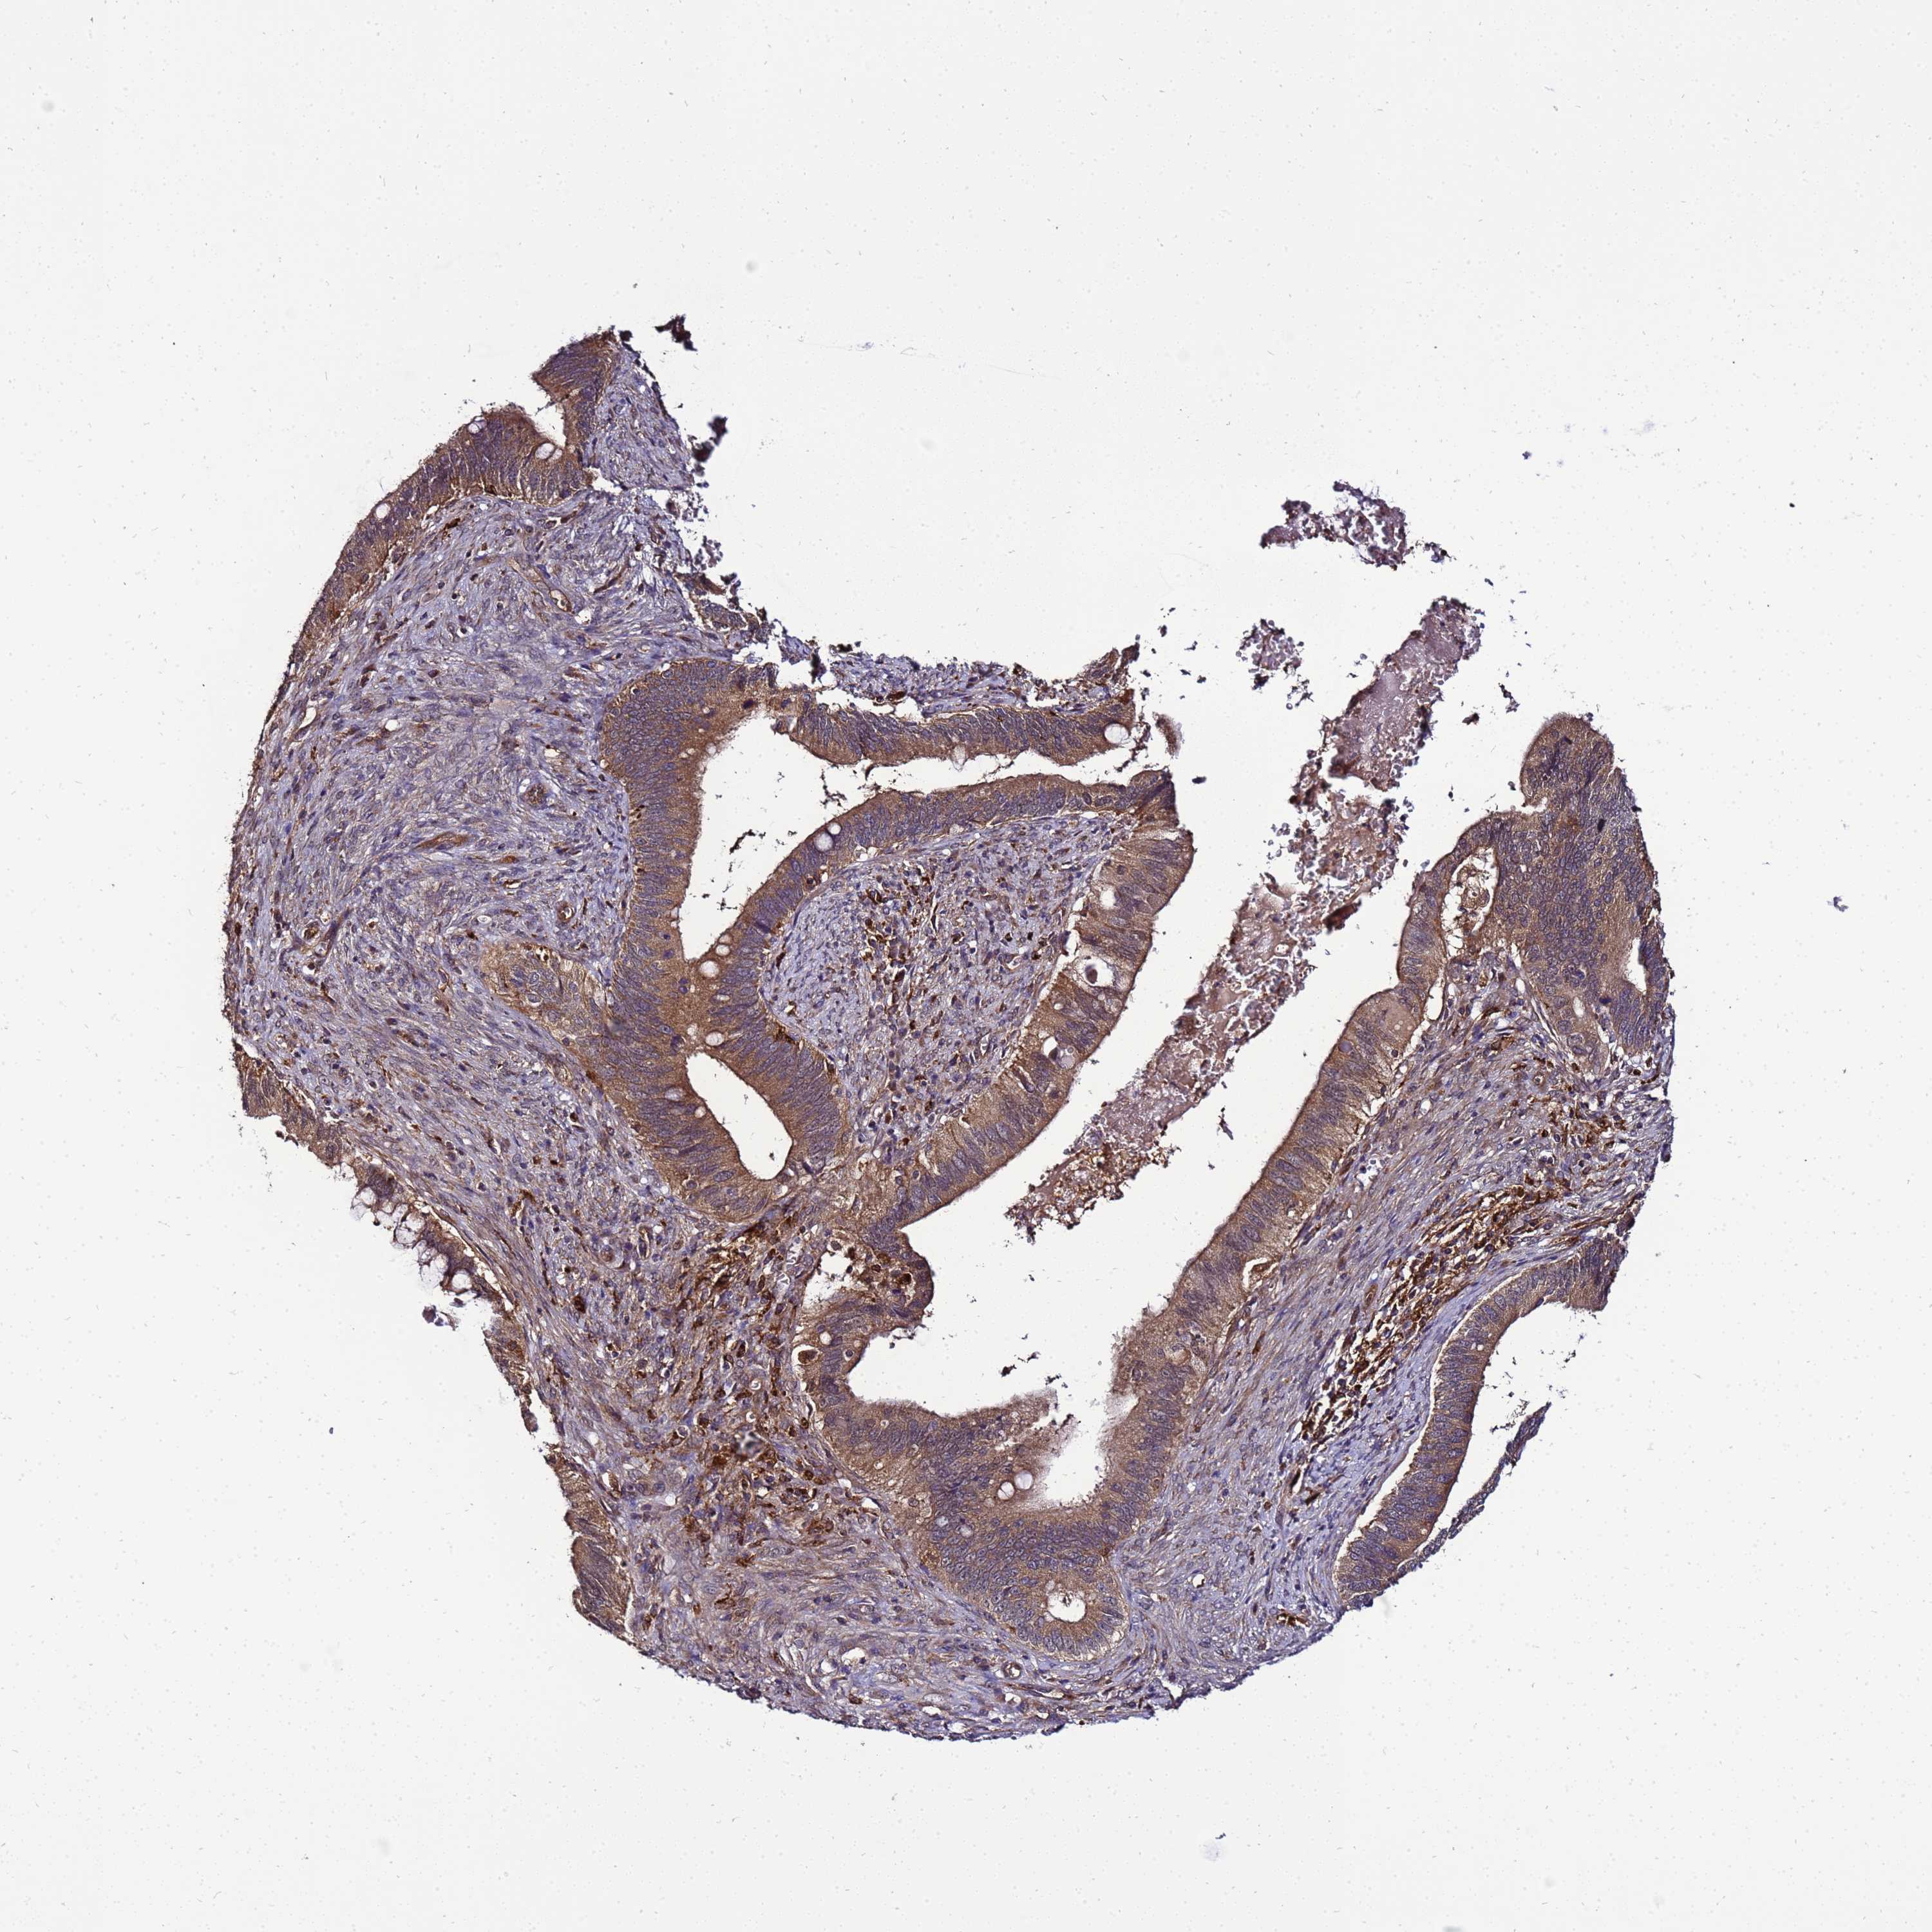

CERVICAL CANCER - Protein expressioni

A mouse-over function shows sample information and annotation data. Click on an image to view it in a full screen mode. Samples can be filtered based on level of antibody staining by selecting one or several of the following categories: high, medium, low and not detected. The assay and annotation is described here.

Note that samples used for immunohistochemistry by the Human Protein Atlas do not correspond to samples in the TCGA dataset.

Antibody stainingi

Antibody staining in the annotated cell types in the current human tissue is reported as not detected, low, medium, or high, based on conventional immunohistochemistry profiling in selected tissues. This score is based on the combination of the staining intensity and fraction of stained cells.

Each image is clickable and will lead to virtual microscopy that enables deeper exploration of all samples and also displays staining intensity scores, fraction scores and subcellular localization as well as patient and tissue information for each sample.

Antibody HPA000822

Staining

High

Medium

Low

Not detected

Intensity

Strong

Moderate

Weak

Negative

Quantity

>75%

75%-25%

<25%

None

Location

Nuclear

Cytoplasmic/membranous

Cytoplasmic/membranous,nuclear

Squamous cell carcinoma, NOS

Adenocarcinoma, NOS